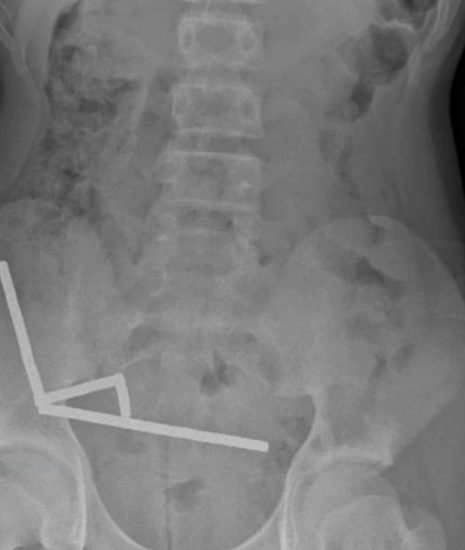

Teen Loses Part of Bowel After Swallowing 80+ Magnets

TUESDAY, Oct. 28, 2025 (HealthDay News) — A young boy in New Zealand needed emergency surgery and lost part of his bowel after swallowing more than 80